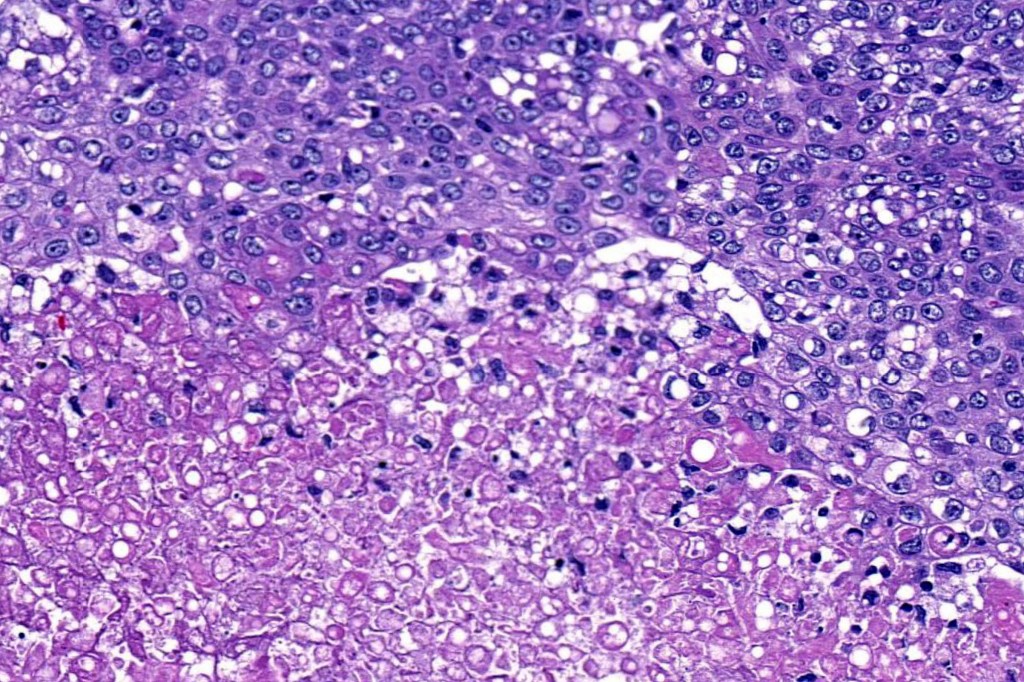

•Well differentiated lobular growth pattern though to a poorly differentiated tumor often showing a diffuse, infiltrating border which may extend into the subcutaneous fat

•Comedo type necrosis commonly present

•Tumors are composed of an admixture of darkly staining basaloid cells with hyperchromatic or vesicular nuclei and more obvious sebaceous cells with eosinophilic, bubbly, multivacuolated cytoplasm frequently indenting the nucleus (scalloped)

•Often mitoses are numerous and abnormal forms evident

Sebaceous carcinoma from a patient with Muir-Torre syndrome kindly shared by Dr. Antonina Kalmykova.